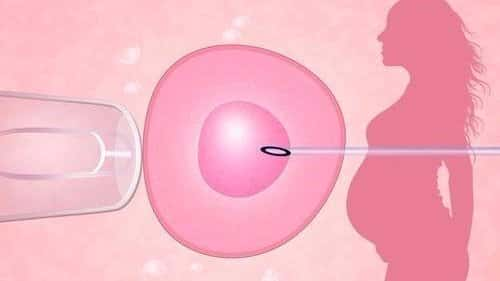

昨晚我们女士来移植咯,女士昨晚是从长春飞到曼谷的, 这一次女士是来移植了,我还记得促排的时候,是我亲自去素万机场接女士的呢,这么快就回来移植了,希望我们女士移植顺利...